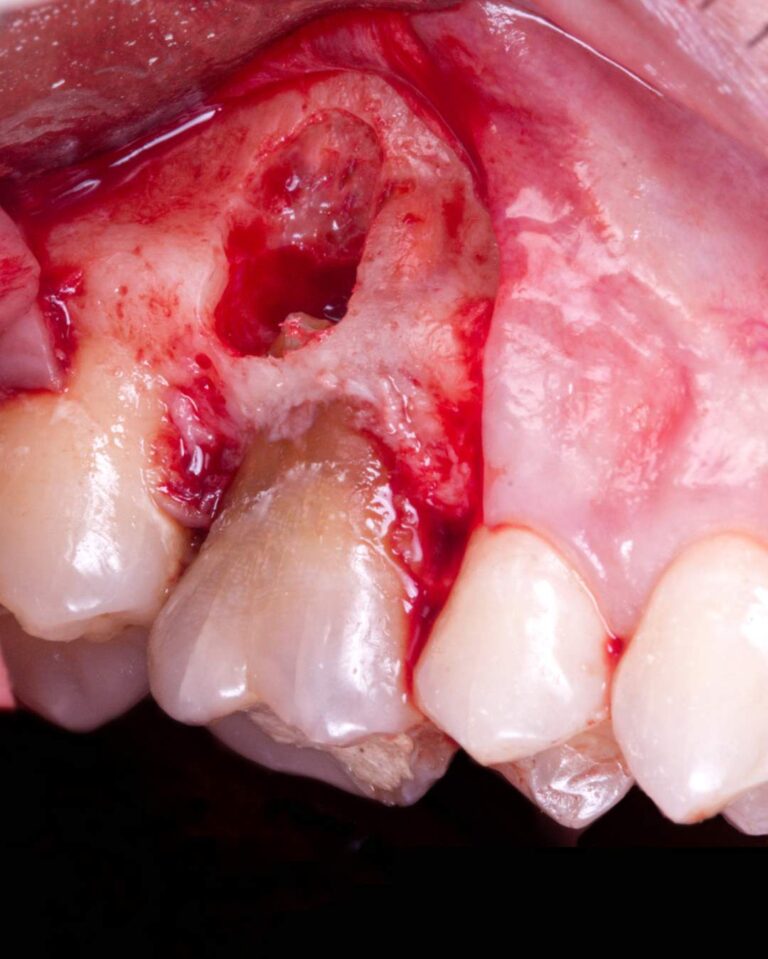

Cirurgia apical para remoção de quisto